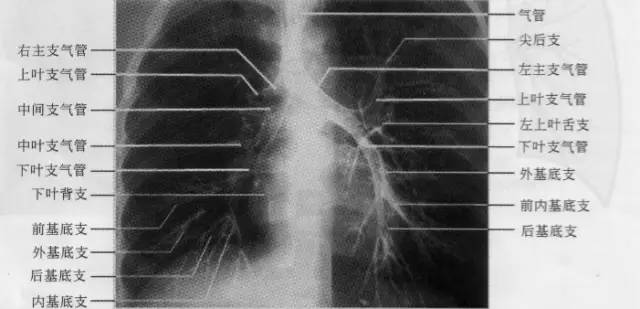

右侧支气管分为上、中、下肺叶支气管及其所属10支肺段支气管。上叶支气管与右主支气管几呈直角向外侧分出,进入上叶后随即分出尖、后、前三支肺段支气管。自上叶开口向下至中叶开口的一段支气管是中间段支气管,无任何分支。自中间支气管下段前壁发出中叶支气管的内、外两支肺段支气管。下叶支气管为中间段支气管的直接延续.宽约1cm,主干甚短,共分为背支、内基底支、前基底支、外基底支和后基底支5支肺段支气管:在正位片上,四基底支自外向内的顺序,依次为前、外、后、内;侧位片上,自前向后依次为前、内、外、后。左侧支气管分为上、下肺叶支气管及其所属8支肺段支气管。左上叶尖后支相当于右上叶的尖支和后支;左下叶前内基底支相当于右下叶的前、内基底支;左侧无中间支气管,相当于右中叶的左上叶舌支直接开口于上叶支气管(如下图)。